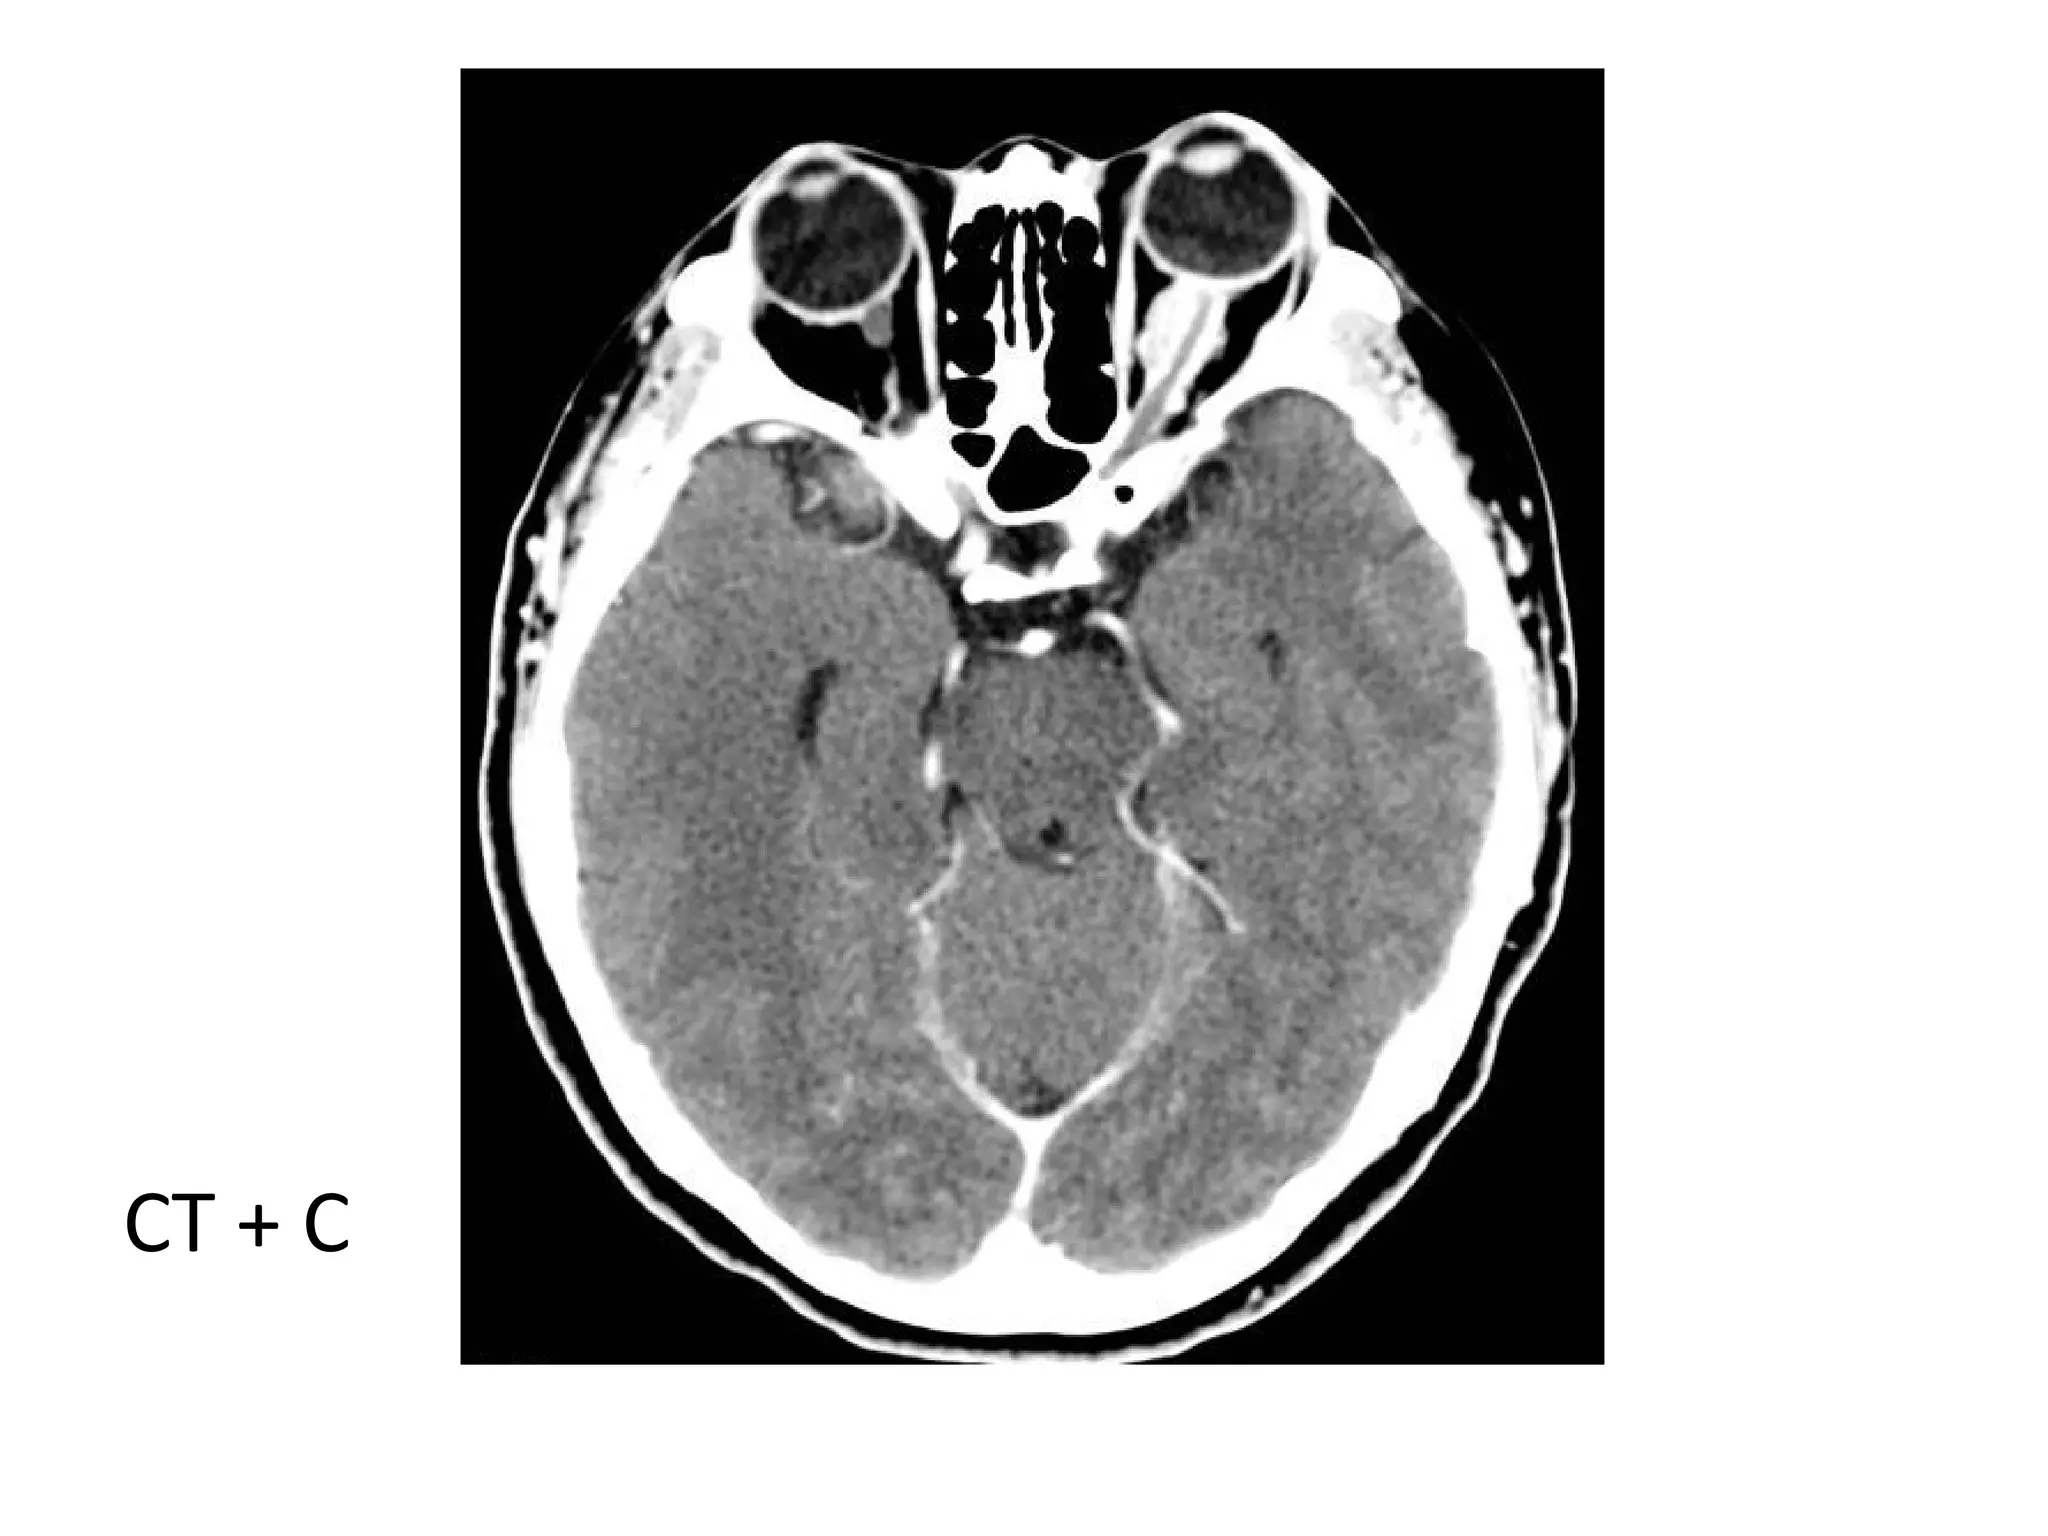

CT + C

Tram track sign